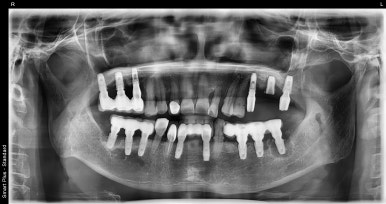

오른쪽 (실제로 왼쪽) 상악 앞니 임플란트 치료 전

2023-01-09

저희 디데이치과에서 치료를 받으신 환자분은 사진상 오른쪽(실제 왼쪽) 앞니 2개(#22, 23) 치아가 불편하신 상태였는데요.

잇몸뼈가 많이 내려앉아있고, 이대로는 더이상 치아를 사용하기 어려울 것으로 판단되어

발치 당일에 임플란트를 식립하면서 뼈이식까지 진행하고, 3개월 후 경과를 보고 보철까지 진행하는 스케줄로 계획해드렸습니다.

통상 상악 앞니같은 경우에는 뼈가 얇고 하악에 비해 무르기 때문에 임플란트 식립부터 보철까지

기간이 4~6개월 이상 걸린다고 생각해주시면 됩니다. 뼈이식이 추가될 경우 더 오래 걸릴 수 있고요.